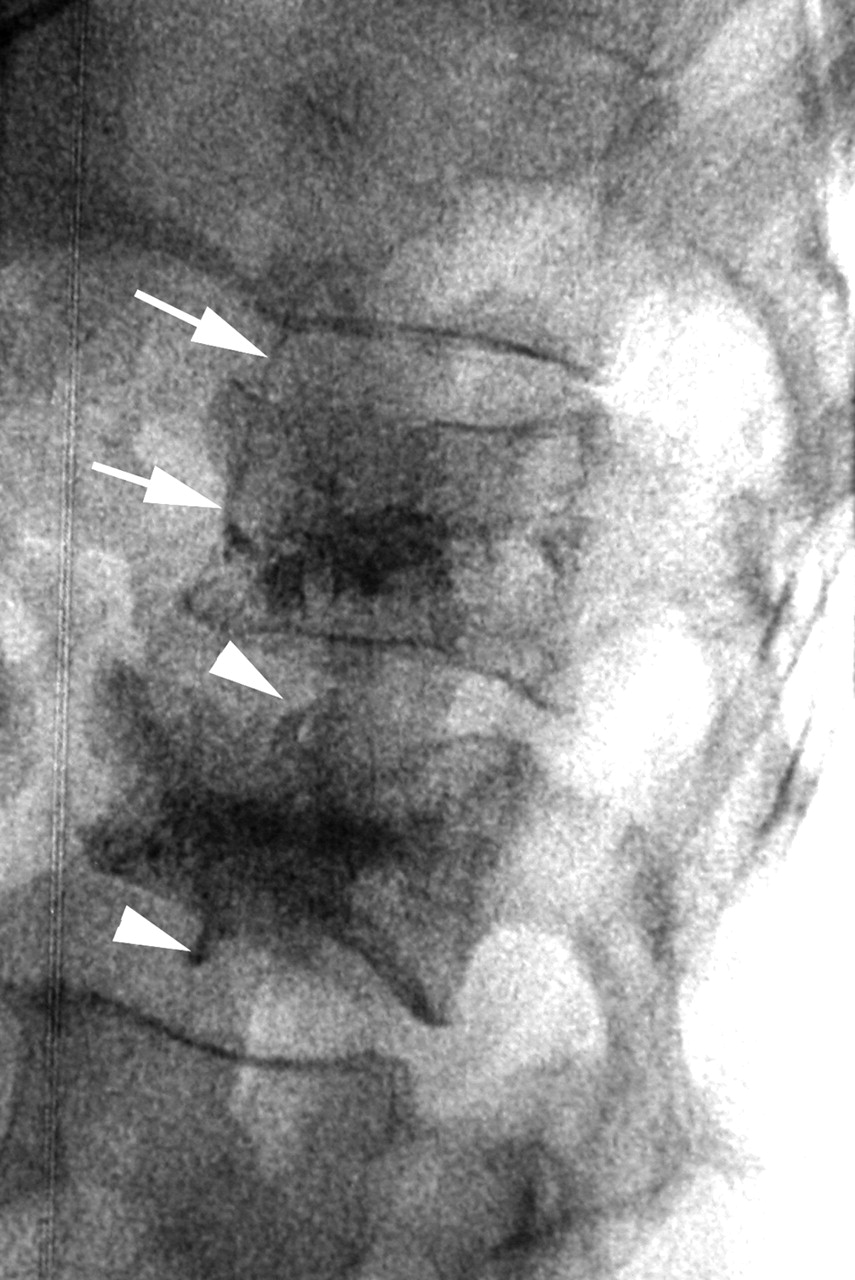

Radiograph following PV and KP, showing small, asymptomatic cement leaks at both levels. The PV level (above) had a small cement leak into an adjacent vein (arrows). The KP level (below) had small cement leaks into both adjacent disk levels (arrowheads).